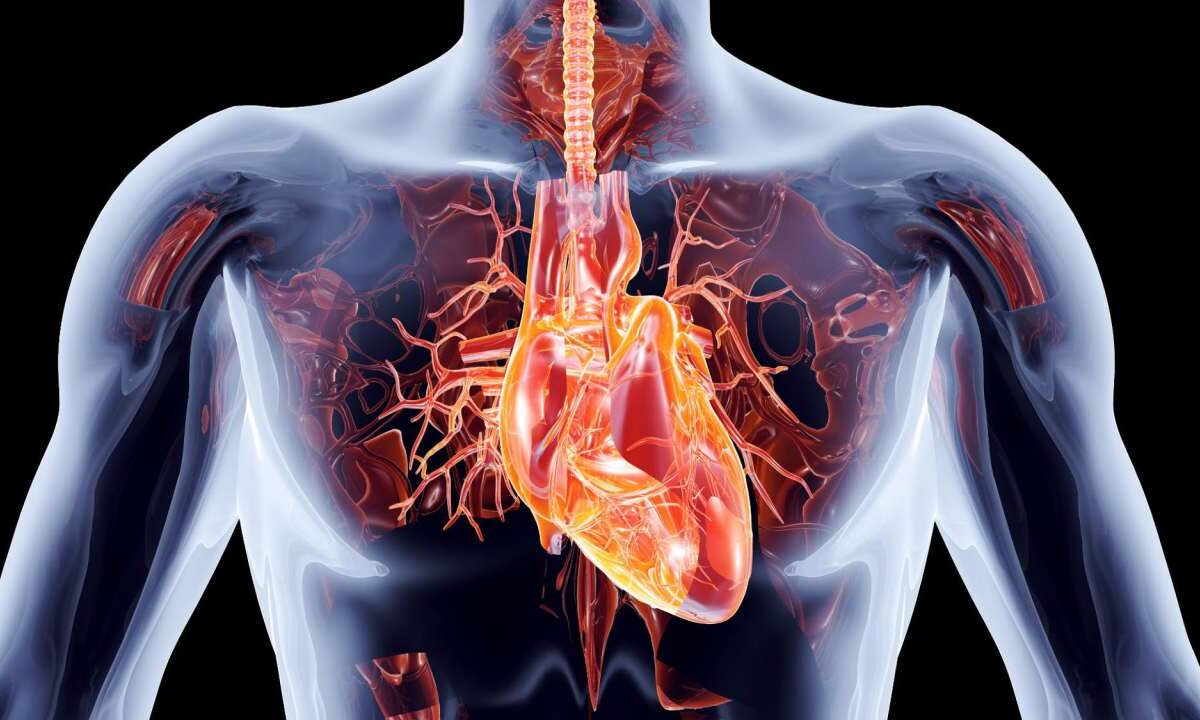

Щоб жити нам необхідний спеціальний насос, який може доставляти життєвоважливу кров в усі частини нашого тіла день і ніч, рік за роком, в обов’язковому порядку. Щоб виконувати цю роботу в тілі живого організму, серце повинно подолати деякі неймовірні інженерні проблеми.

Наше життя висить на волосинці. Постійний потік збагаченої крові повинен досягати клітин по всьому тілу, доставляючи кисень і необхідні поживні речовини нашим кінцівкам, видаляючи відходи, такі як вуглекислий газ. Зупиніть потік всього на кілька хвилин, і життя припиниться.

Як Творець забезпечив цей стійкий потік? Він дав нам насос з м’якої плоті, а не з твердої сталі. За різними підрахунками цей потужний м’яз проштовхує кров через, принаймні, 1 500 миль (2 500 км) кровоносних судин, деякі з яких завтовшки в одну червону кров’яну клітину. Серце має битися 100 000 разів на день невтомно і без збоїв.

Серце — це два насоси в одному. В утробі матері серце дитини починається як проста велика трубка. Однак, у міру того, як немовля росте, Творець спроектував трубку так, щоб вона вигиналась назад. Сторони зливаються між собою, і утворюється стіна між двома відділами. В міру того, як серце формується, дві сторони залишаються окремими частинами, по суті стаючи двома окремими насосами.

У кожному з цих насосів є своя двокамерна система відкачування (мал. 1). М’язи в одній камері скорочуються, в той час як м’язи в іншій камері розслабляються і таким чином кров переливається з однієї камери до іншої. Серце постійно вичавлює кров звивистим рухом подібним до того, як вичавлюють ганчірку. Віджимати рідину значно ефективніше, ніж відразу викачувати, як це роблять звичайні насоси. Та ж сама дія вичавлює кров з обох насосів: заповнюючи одну камеру, одночасно стає вільною інша. Але саме це створює проблему. Ліва сторона повинна створювати в шість разів більше сили, ніж права сторона, щоб переміщати кров по всьому тілу.1 (Більше сили необхідно, бо перемістити кров до дальніх частин тіла важче, ніж зробити це до прилеглих легень). Для компенсації ліва частина серця була створена мати більш потужні м’язи.

Серце складається з двох відділів, які качають кров через дві окремі камери — передсердя і шлуночка. Коли одна з камер наповнюється, друга стискається, видавлюючи кров. Оточує серце захисний шар під назвою навколосерцева сумка.